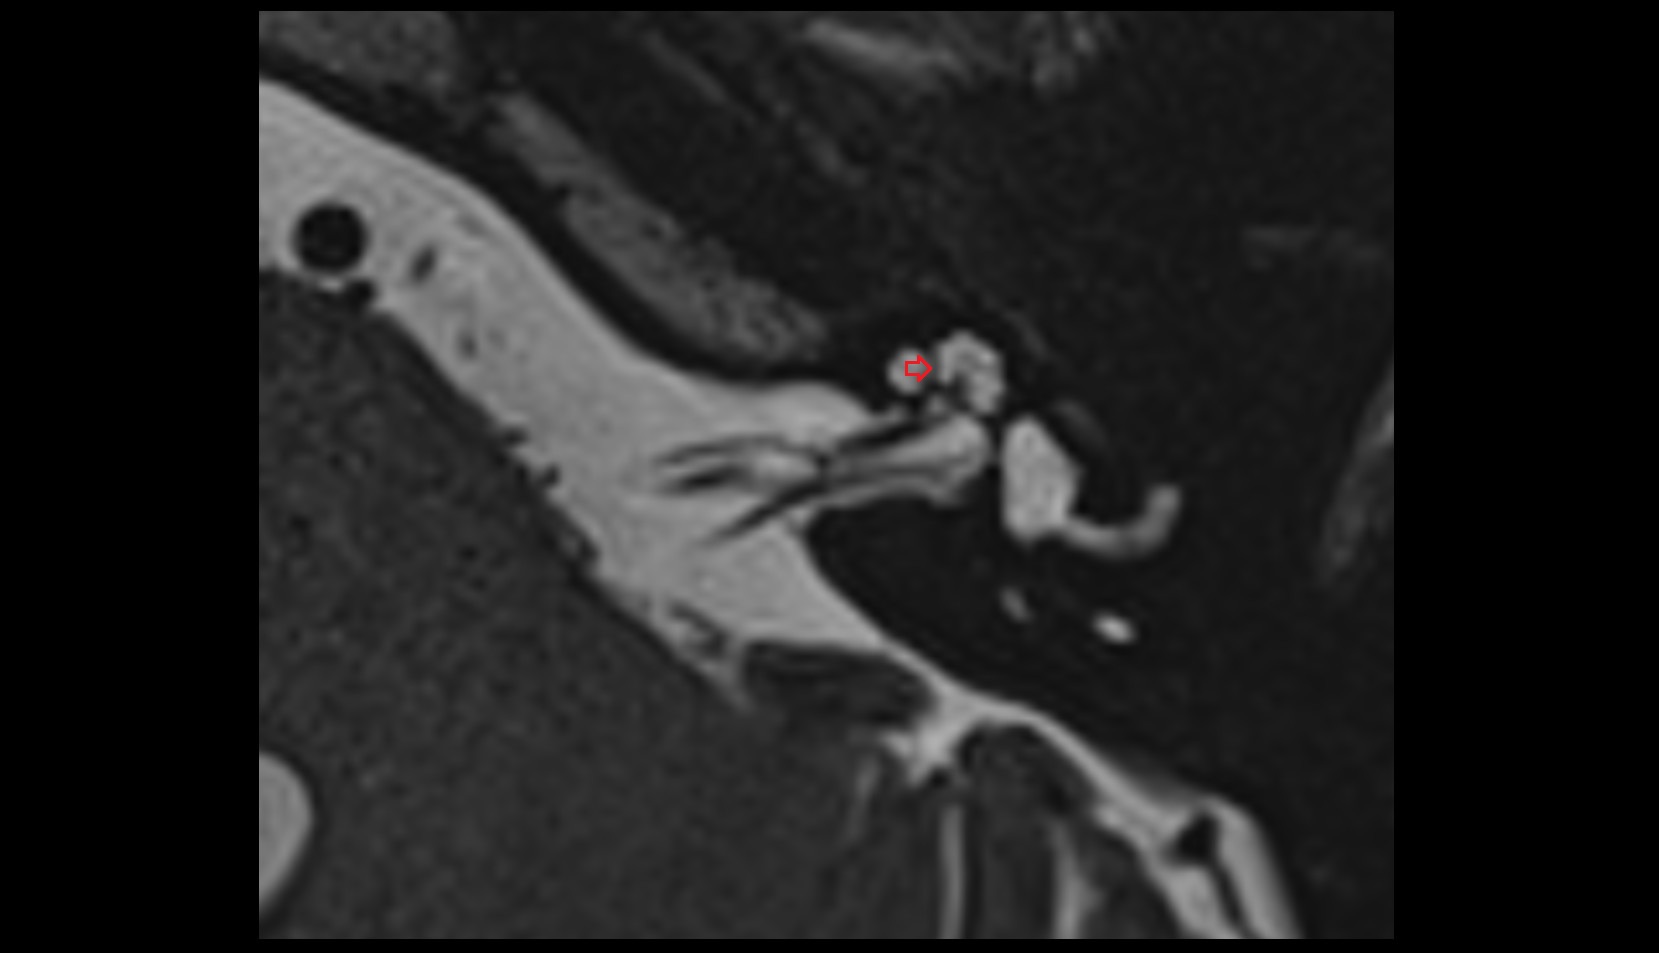

- Temporomandibular joint

- Mandibular condyle

- Mandibular fossa

- Articular disc of temporomandibular joint

- Articular eminence

- Intermediate zone of articular disc

- Superior retrodiscal layer